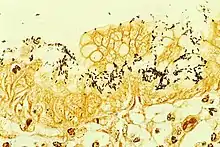

Helicobacter pylori colonized on the surface of regenerative epithelium, stained with the Warthin-Starry method.

Warthin–Starry stains organisms dark brown to black, and the background light golden brown/golden yellow.[5]